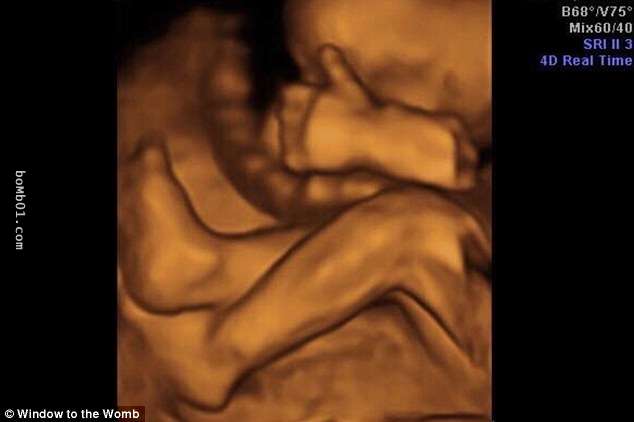

▼這個寶寶手腳並用,擋住了自己的臉。